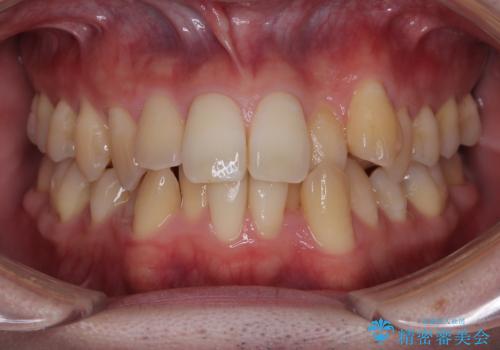

最新の症例

Latest cases